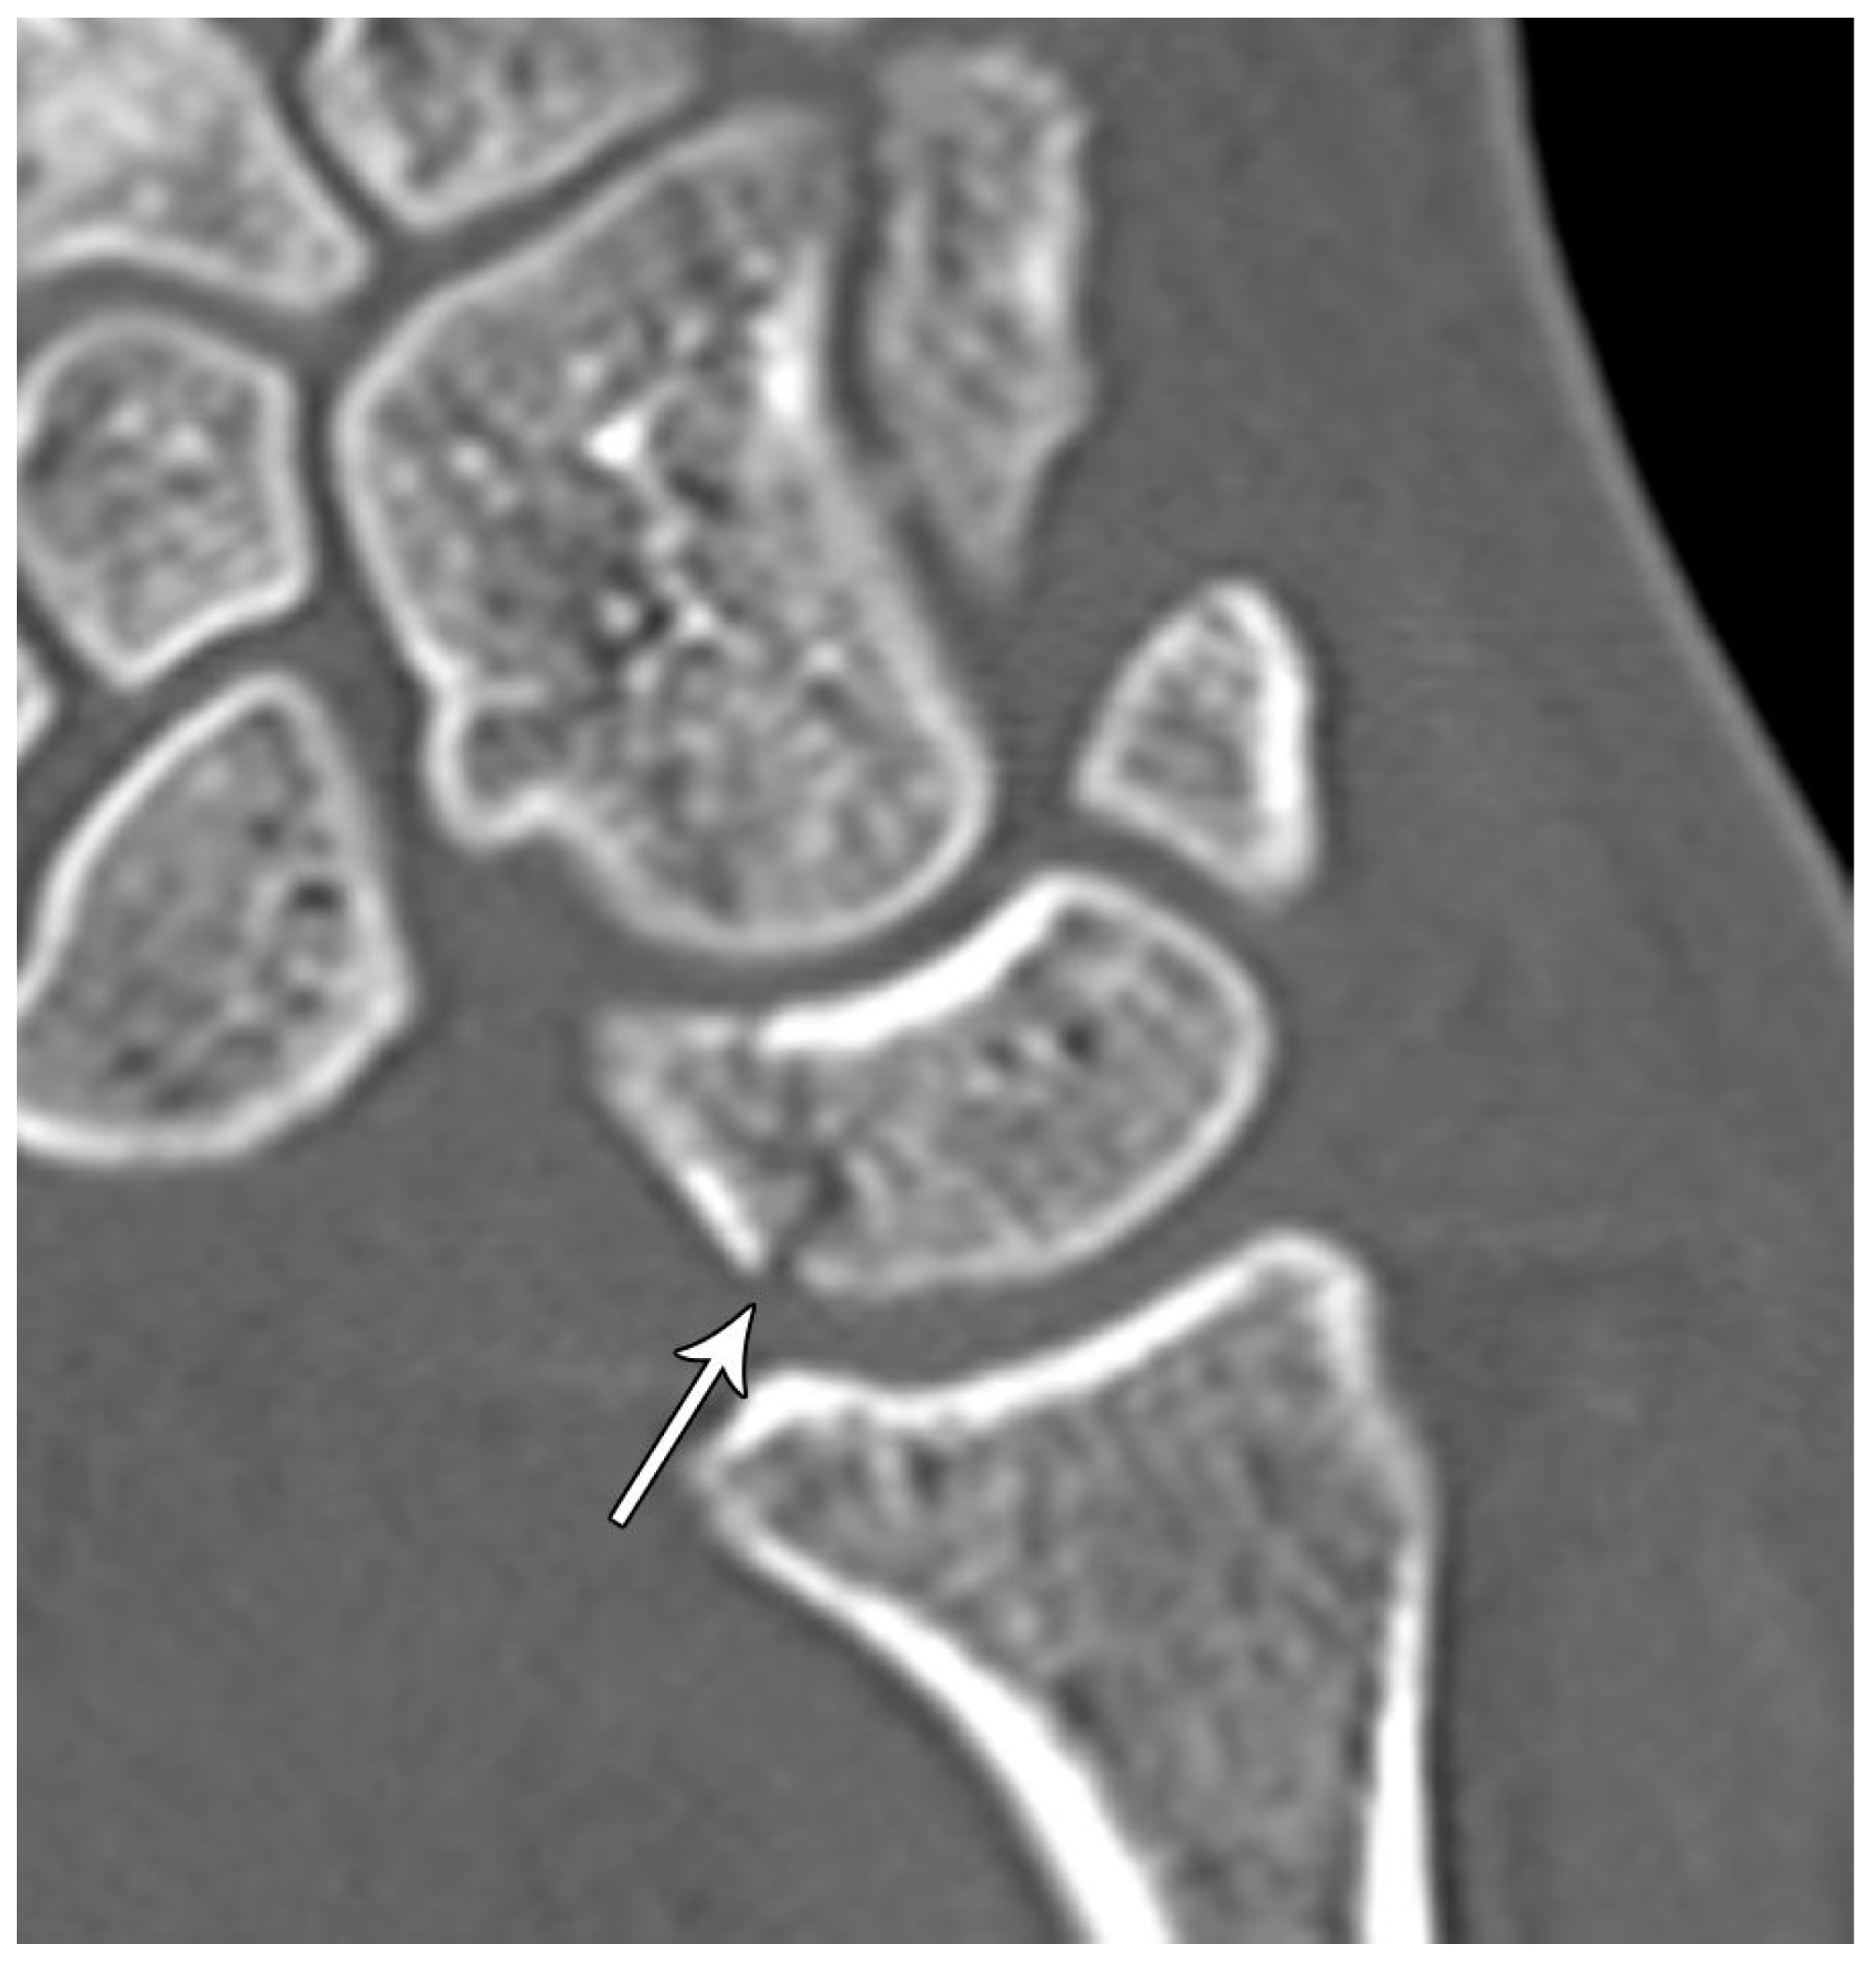

The majority of scaphoid fractures (70%) occur through the waist of the scaphoid, with 10% of scaphoid fractures involving the distal third, and 20% involving the proximal third (Figure 2 and Figure 3) [2,14]. With a scaphoid waist fracture, dorsal prominence at the fracture site due to dorsal angulation is known as humpback deformity (Figure 4). This deformity is important to recognize, as it needs to be more aggressively managed due to high risk of nonunion [15]. Additionally, if the two fragments unite with a humpback deformity, it may further destabilize the wrist. This humpback deformity may also be associated with dorsal intercalated segment instability (DISI), which will be covered in more detail later.

Figure 4. (a) Lateral radiograph of the wrist showing Humpback deformity (arrow) after a scaphoid fracture. (b) Sagittal CT reformation of the wrist showing the full extent of a humpback deformity with dorsal prominence at the site of the scaphoid fracture (arrowheads); image courtesy of Frank Gaillard, Radiopaedia.org, rID: 18269.